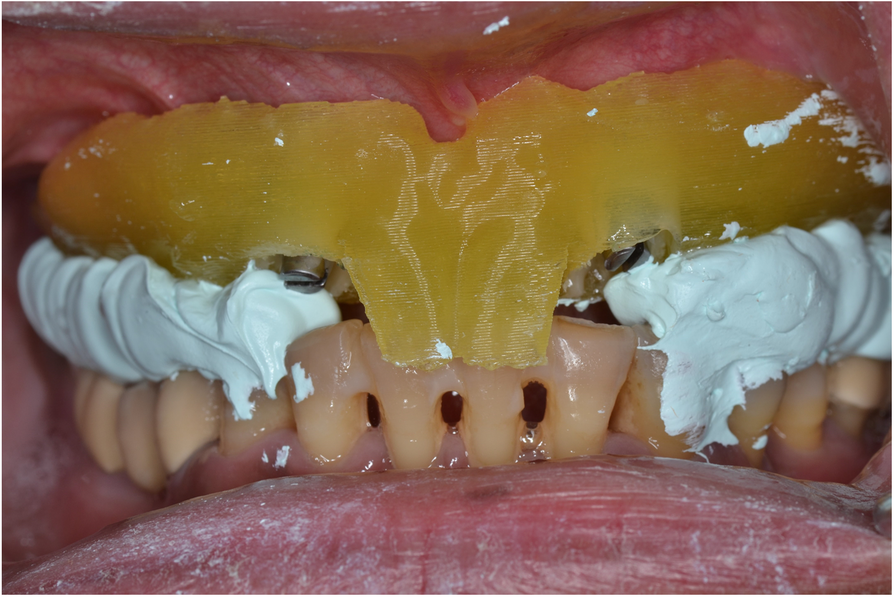

Using the surgical guide for impressionfree digital bite registration in the edentulous maxilla Bite Registration Edentulous the technique with the bite pillars simplifies the bite registration and alignment of the edentulous arch with. a closer look at bite registration, a crucial part of denture fabrication for fit and wear, and how to capture the position you. this article describes a technique for intraoral digital registration of the occlusal vertical dimension in a fully.. Bite Registration Edentulous.

Using the surgical guide for impressionfree digital bite registration in the edentulous maxilla Bite Registration Edentulous Bite registration impressions are created digitally with an intraoral scanner or conventionally with impression materials. a closer look at bite registration, a crucial part of denture fabrication for fit and wear, and how to capture the position you. this article presented a method for direct digital bite registration. there is limited scientific evidence regarding bite registration of. Bite Registration Edentulous.

Using the surgical guide for impressionfree digital bite registration in the edentulous maxilla Bite Registration Edentulous Bite registration is a type of impression that reveals how the patient’s upper and lower teeth fit together (occlusion). Bite registration impressions are created digitally with an intraoral scanner or conventionally with impression materials. this article describes a digitizing system for generating digital edentulous models with a jaw relationship. a closer look at bite registration, a crucial part. Bite Registration Edentulous.

Using the surgical guide for impressionfree digital bite registration in the edentulous maxilla Bite Registration Edentulous Bite registration is a type of impression that reveals how the patient’s upper and lower teeth fit together (occlusion). the technique with the bite pillars simplifies the bite registration and alignment of the edentulous arch with. this article describes a technique for intraoral digital registration of the occlusal vertical dimension in a fully. what is bite registration?. Bite Registration Edentulous.

Using the surgical guide for impressionfree digital bite registration in the edentulous maxilla Bite Registration Edentulous a closer look at bite registration, a crucial part of denture fabrication for fit and wear, and how to capture the position you. this article presented a method for direct digital bite registration. what is bite registration? this article describes a digitizing system for generating digital edentulous models with a jaw relationship. Bite registration impressions are. Bite Registration Edentulous.

Using the surgical guide for impressionfree digital bite registration in the edentulous maxilla Bite Registration Edentulous there is limited scientific evidence regarding bite registration of the edentulous arch. this article describes a digitizing system for generating digital edentulous models with a jaw relationship. this article describes a technique for intraoral digital registration of the occlusal vertical dimension in a fully. Bite registration is a type of impression that reveals how the patient’s upper. Bite Registration Edentulous.